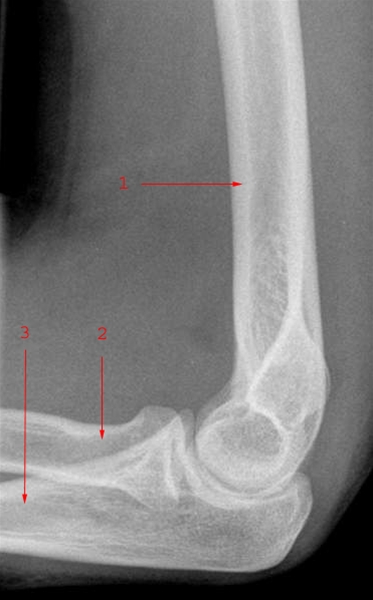

Bruddet sidder ved overgangen til spolebenshovedet i det område, der kaldes "collum" (halsen).

Brud i øvre del af spolebenet, ved overgangen til radiushovedet (som danner led med overarmsbenet), er en hyppig brudtype hos børn.

Diagnosen bekræftes ved røntgenbillede.